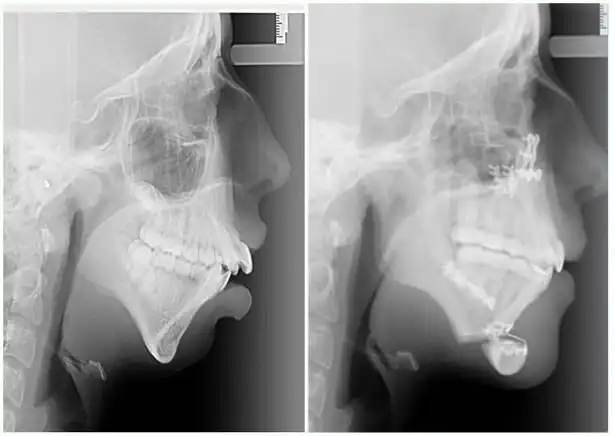

Девушка по имени Элли Джонс (Ellie Jones) родилась с врожденным состоянием лица, которое отразилось на том, что в возрасте 8 лет челюсть Элли просто перестала расти. В результате этого кости нижней части лица девушки перестали развиваться должным образом и были меньше нормального размера. Этот недуг был обнаружен ортодонтом, который сразу догадался в чём проблема, как только девушка пришла к нему на установку скобок в 14 лет.

В течение следующих 6 лет Элли посещала челюстно-лицевого хирурга Эмму Вулли из госпиталя Глан Клвид, Британия, изменить не только свою челюсть, но и жизнь. Предлагаем вам взглянуть на фантастические результаты, которых им удалось добиться.

Первую операцию по преобразованию челюсти Элли перенесла в 16 лет.

Операция заключалась в вырезании челюсти по горизонтали и вертикали с последующим ещё большим хирургическим вмешательством.

Несмотря на боль от операций, Элли говорит, что в восторге от результатов: "Я почувствовала облегчение, наконец-то я чувствую, что могу быть самой собой. Я была очень застенчивой, но теперь я чувствую себя гораздо увереннее. Это изменило мою жизнь". "Многие люди даже не догадываются о том, что имеют дефект челюсти и думают, что у них есть просто проблемы с прикусом. Если не обратить на это внимание в раннем возрасте, то это может принести реальные трудности в будущем", — сказала хирург Эмма Вулли